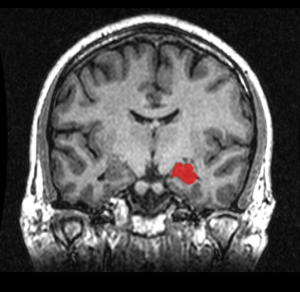

One specific example of this type of new diagnostic approach involves depression. It is possible that depression is relation to the specific region of the cingulate cortex (the sub-genual anterior cingulate cortex). This research attempts to treat the mood disorder with specific electrical stimulation of this region through deep brain stimulation with implanted brain electrodes and use of MRIs. Other research uses brain stimulation from the surface (without invasive electrodes) in the lateral pre frontal region. This latter treatment has been approved by the FDA with transcranial magnetic stimulation (TMS) when the depression is extremely severe and does not respond to any conventional treatment. Another use of imaging for treatment is using it as feedback to individuals to study treatment of pain and depression.